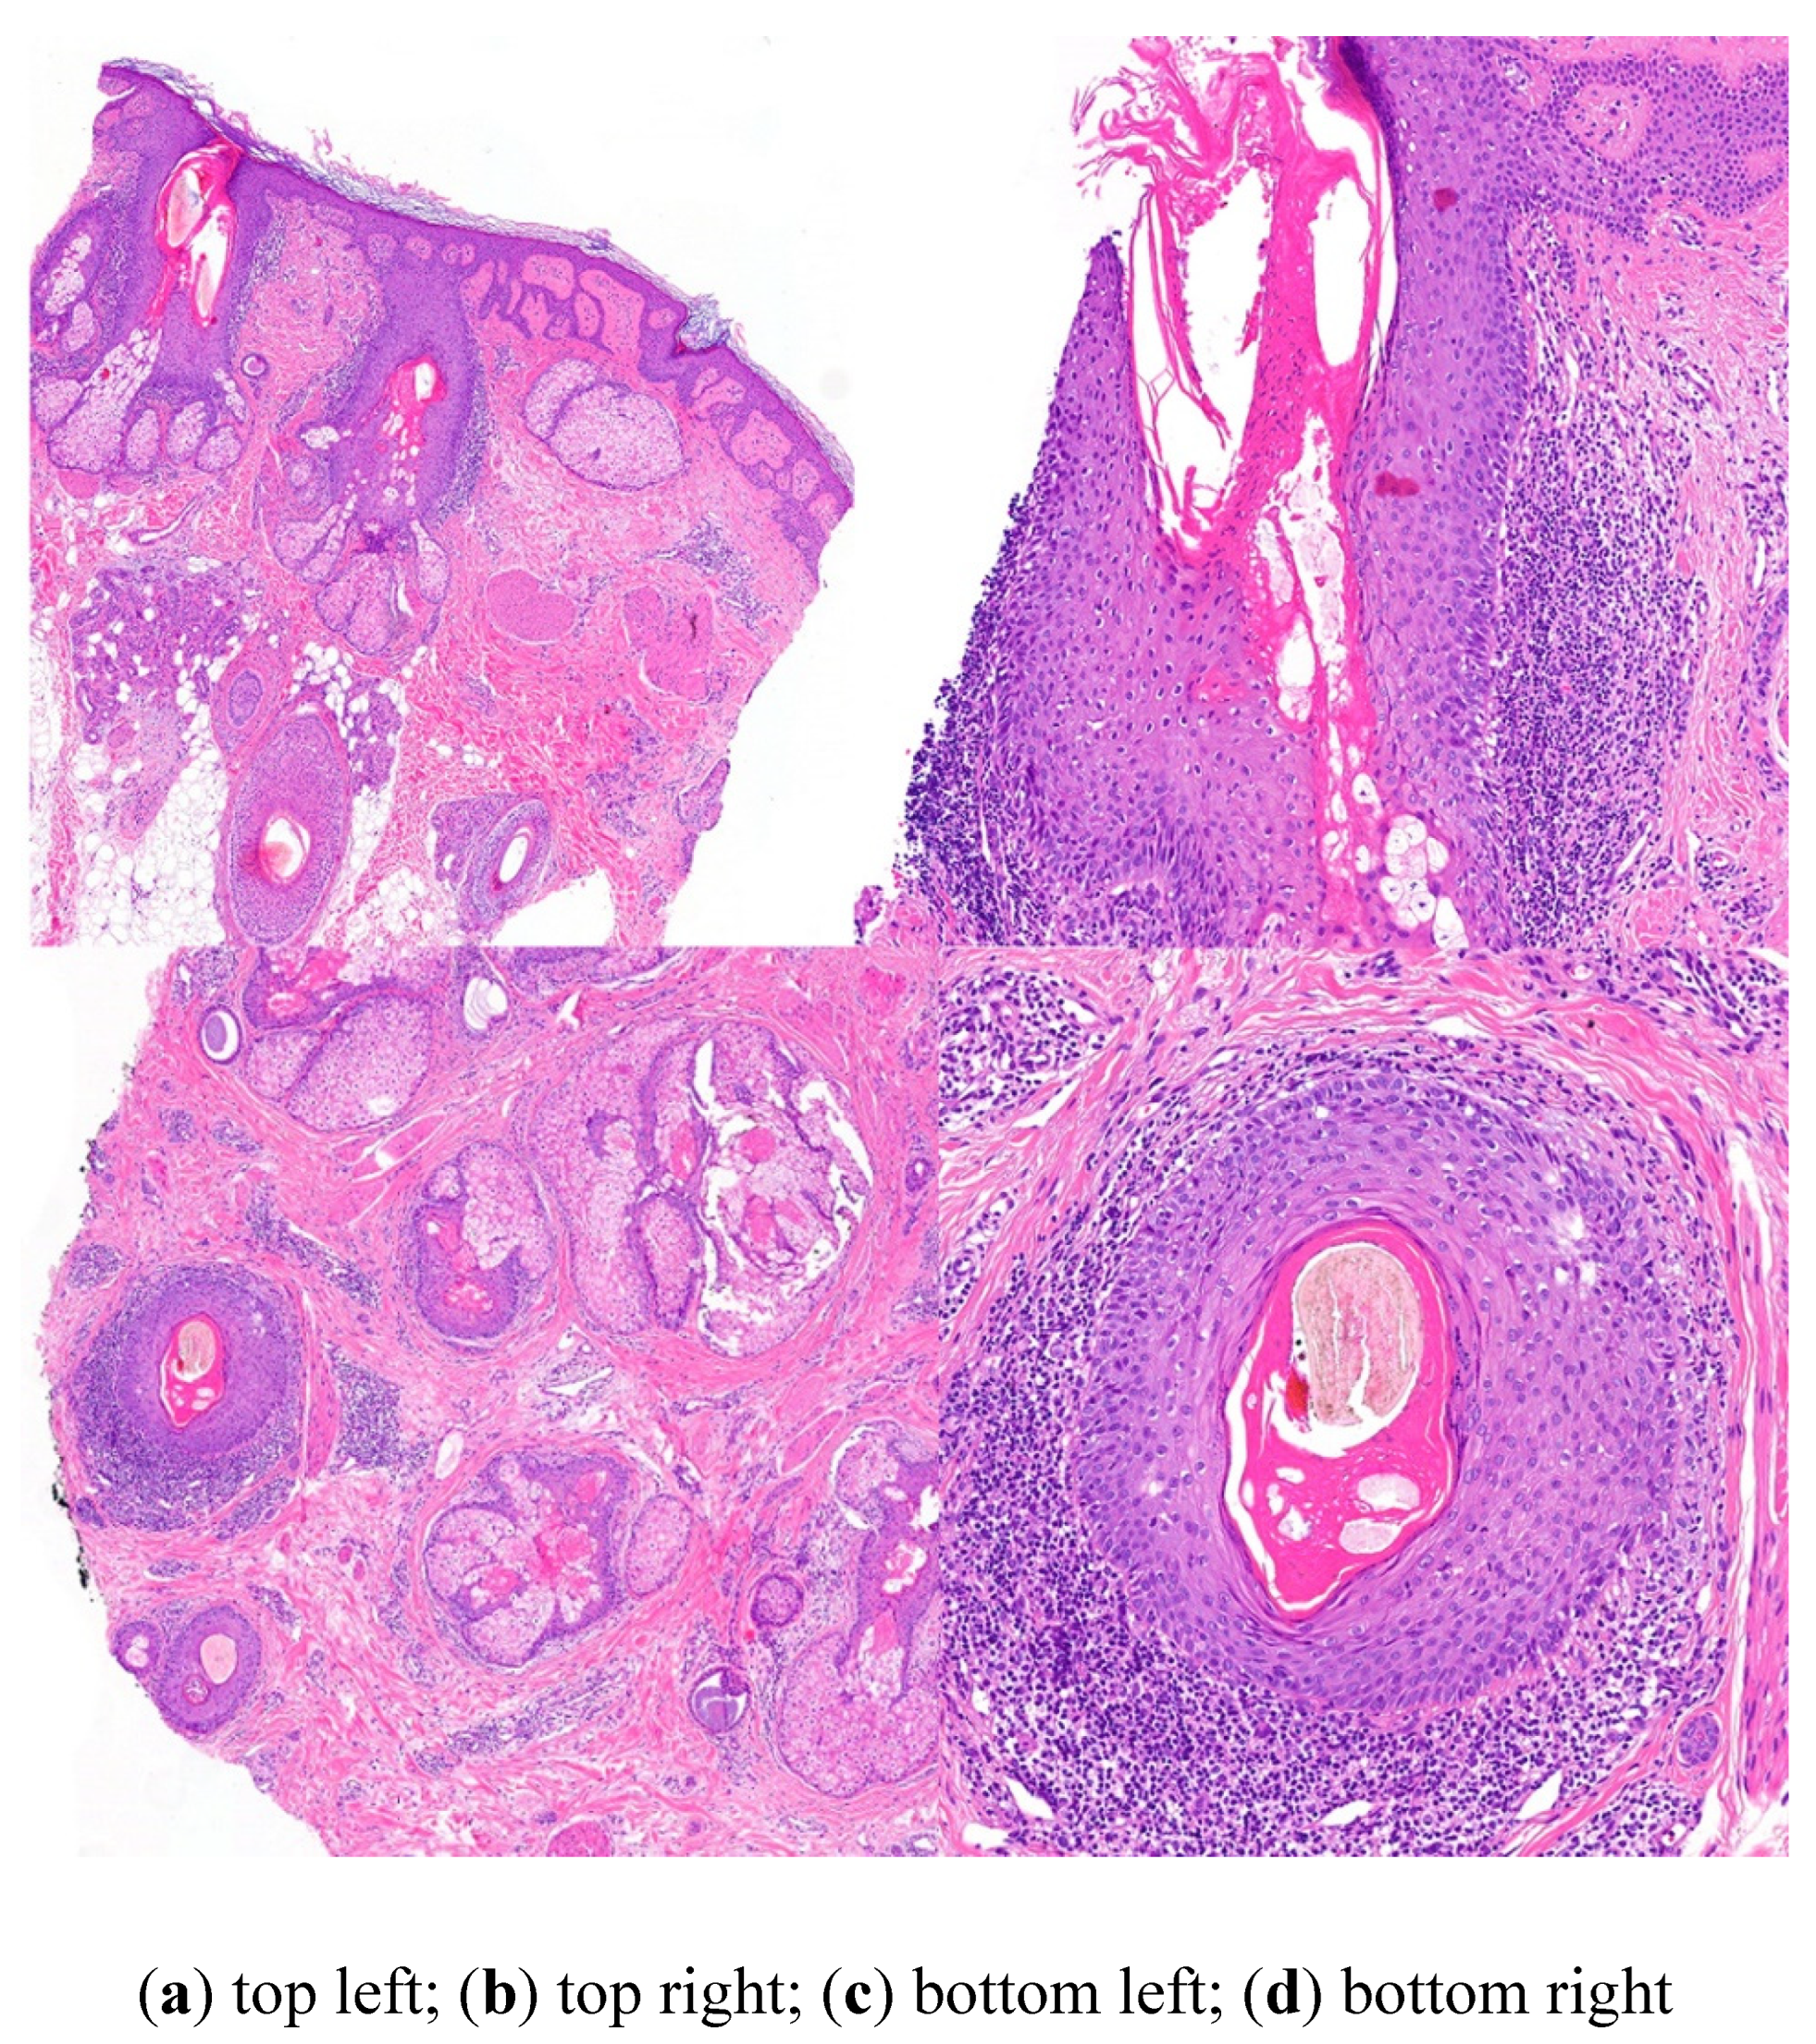

4. Adequate Hair Biopsy